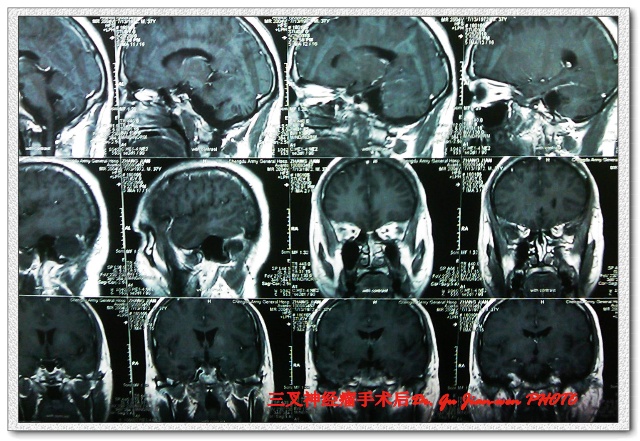

该例术后影像